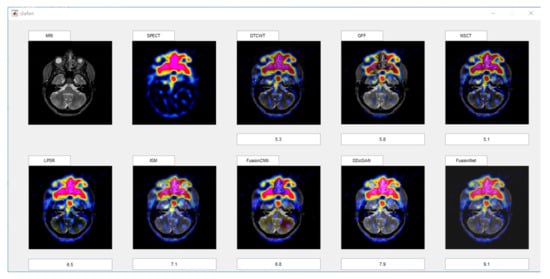

Subjective evaluation methods generally rely on doctors in the field of organizing medical imaging to evaluate the visual effects of fused images. The evaluation method is relatively reliable. After all, the evaluation results are based on the doctors’ years of experience. However, there are also differences in the scores caused by the difference between the field of personal expertise and the research direction. The objective method predicts the visual quality of the fused image by modeling the human visual system, which can avoid the disadvantages of the subjective method. However, due to the complexity of the human visual system, modeling is impossible, so the evaluation result will deviate from human judgment. In our experiment, we used the above two methods to compare our algorithm with another seven representative algorithms. In order to minimize the interference of other factors on the subjective evaluation, we selected 10 male doctors and 10 female doctors in different hospitals, all of whom were from the medical imaging department. In order to reduce the impact of the environment on them, the assessment work is carried out in the same office. All images will be displayed on the computer monitor at the same resolution, so that you can ensure that everyone sees the same quality fused image. Scoring is done on a MATLAB GUI, which provides an enlarged tool for doctors to check details. The GUI is shown in Figure 5.

Figure 5.

Interface of subjective scoring system.

Doctors could give a score between 1 and 10 based on the texture, detail, and color changes in the fused image. For each fusion image, we will calculate its average score and variance as its subjective score. In view of the fact that there are three types of our functional images in the experiment, in the corresponding three types of fused images, we will select four groups of representative fused images for subjective scoring for each type.